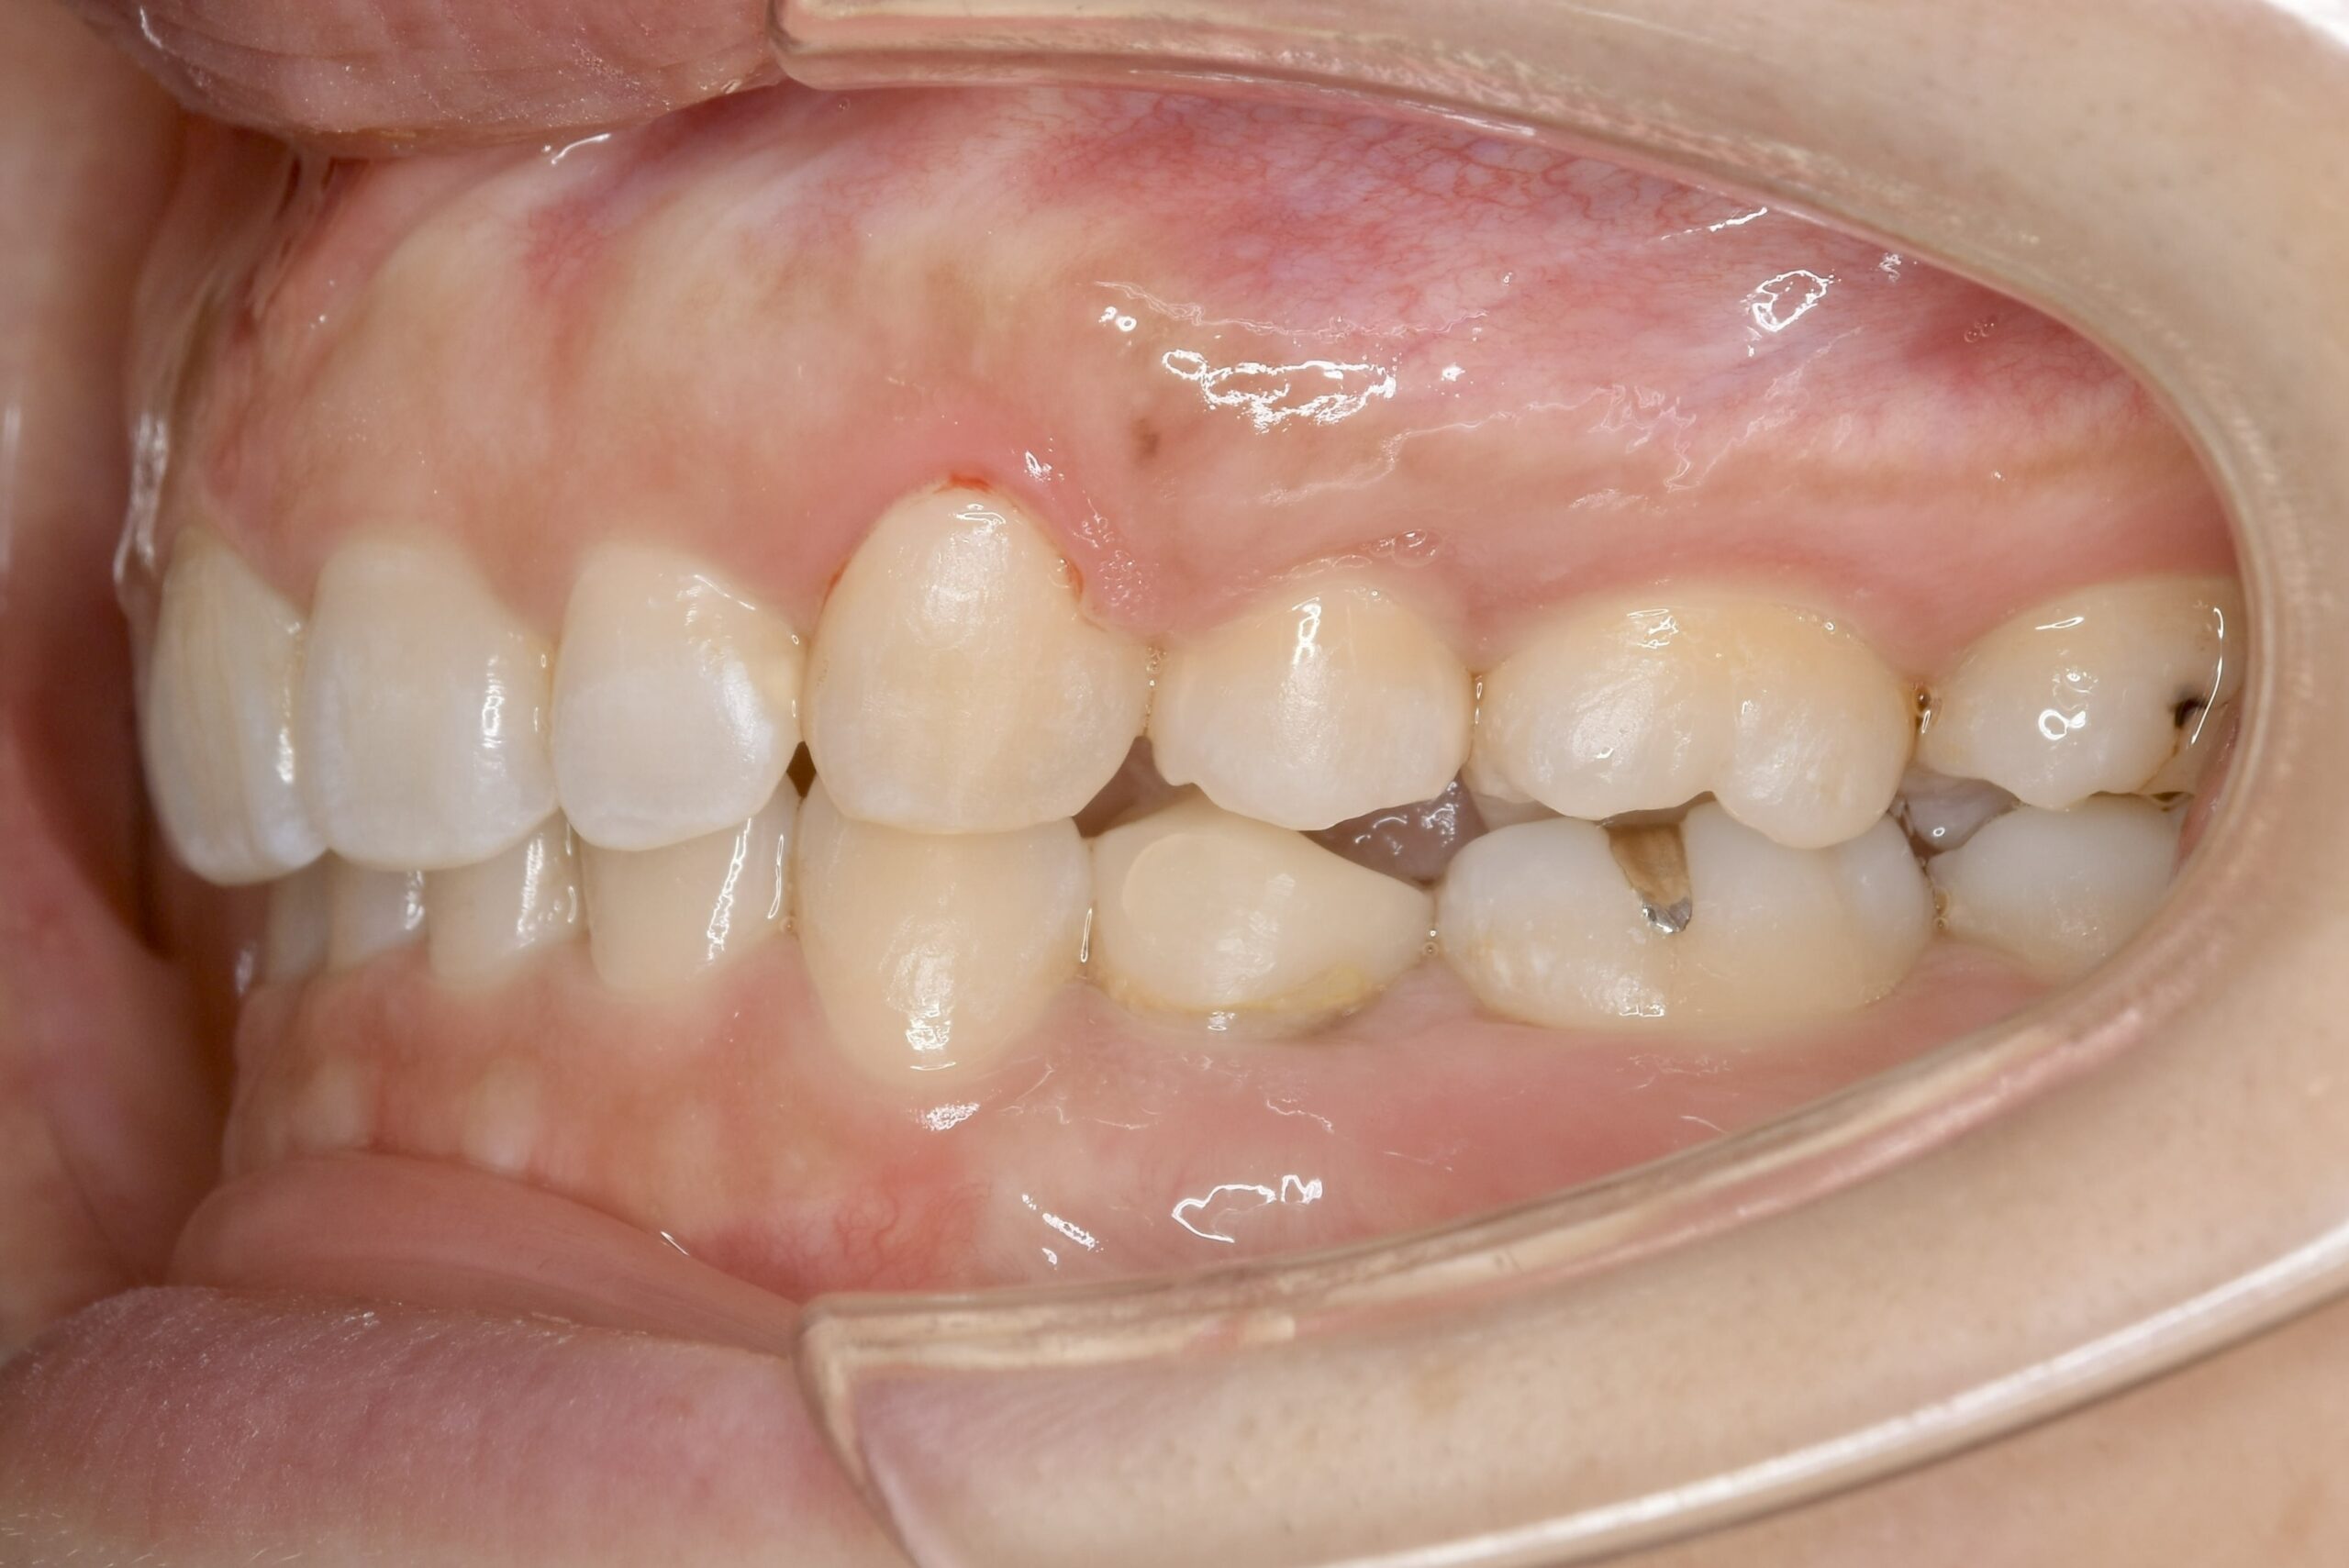

32歳 女性 治療期間:1年7ヶ月

BEFORE

主訴 口元が出ていて気になる。

診断名・主な症状 叢生を伴う上顎前突

治療内容 上下とも歯を2本抜いて、上の前歯を後方に引きながら、でこぼこを治しました。

使用装置 マウスピース矯正装置(インビザライン)

抜歯部位 上 両側4番目

下 右側4番目、左側5番目

治療期間 1年7ヶ月

通院回数 13回

費用 91万円程度(税別)   270

リスク・副作用 痛み、歯肉退縮、歯根吸収、抜歯に伴う出血や腫れが生じることがあります。